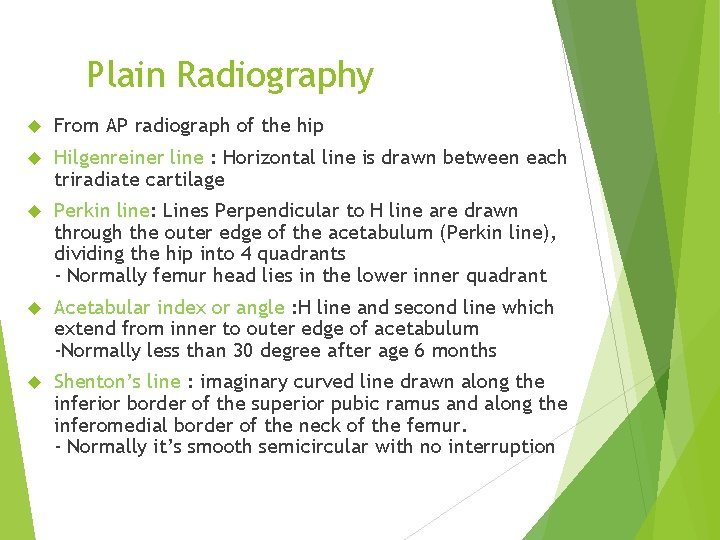

Plain Radiography From AP radiograph of the hip Hilgenreiner line : Horizontal line is drawn between each triradiate cartilage Perkin line: Lines Perpendicular to H line are drawn through the outer edge of the acetabulum (Perkin line), dividing the hip into 4 quadrants - Normally femur head lies in the lower inner quadrant Acetabular index or angle : H line and second line which extend from inner to outer edge of acetabulum -Normally less than 30 degree after age 6 months Shenton’s line : imaginary curved line drawn along the inferior border of the superior pubic ramus and along the inferomedial border of the neck of the femur. - Normally it’s smooth semicircular with no interruption